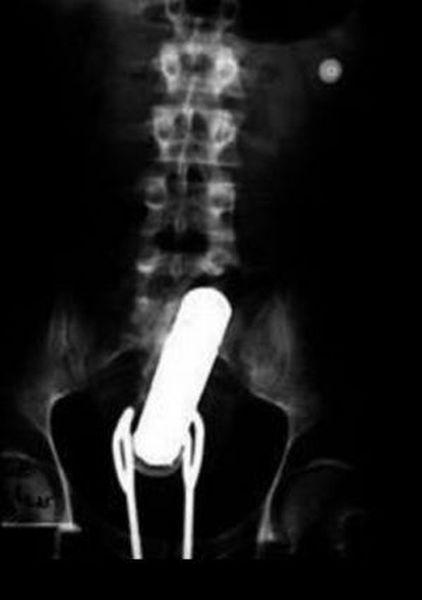

Предметы, которые можно обнаружить в человеке благодаря рентгену

Внутри человека с помощью рентгенологического оборудования можно обнаружить массу оригинальных предметов, причем порой даже несовместимых с жизнью.

Неопознанное